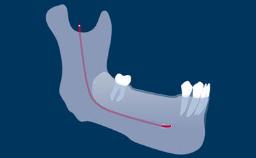

There are therefore specific challenges to overcome when they are prescribed. This is particularly the case with partial RDPs in Kennedy Classifications I, II, and IV of partial edentulism where one or more of the strategic natural tooth abutments are missing.

- identify strategic placement positions for implants in Kennedy Class I, II, and IV partial RDP designs